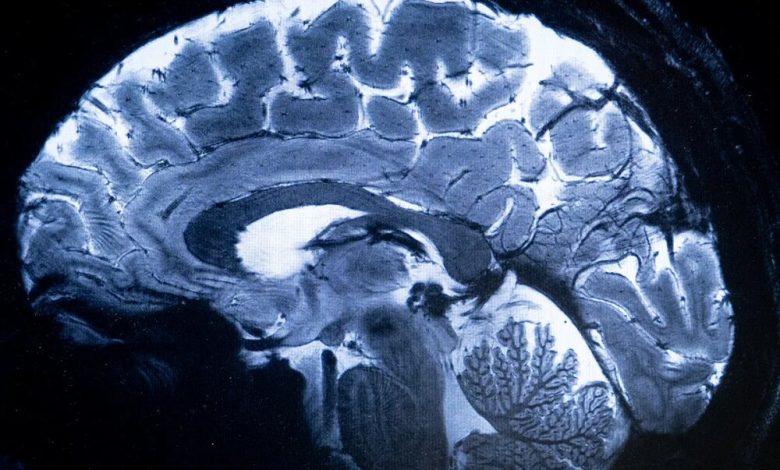

چهاردهمین کنگره علوم اعصاب پایه و بالینی با حمایت ستاد توسعه علوم و فناوریهای شناختی از ۱۹ آذر در تهران گشایش می یابد.

به گزارش مجله اینترنتی مفید، چهاردهمین کنگره علوم اعصاب پایه و بالینی به منظور توسعه فعالیتهای پژوهشی، تبادل آخرین دستاوردها و یافته های تحقیقاتی و نیز گسترش تعامل و همکاری میان محققان، متخصصان و پژوهشگران با حمایت ستاد توسعه علوم و فناوریهای شناختی از ۱۹ تا ۲۱ آذرماه در محل مرکز همایشهای بین المللی رازی دانشگاه علوم پزشکی ایران برگزار می شود.

این کنگره با محوریت “پزشکی شخصی سازی شده”، فرصت مناسبی را برای محققان، پزشکان، دانشجویان و متخصصان فعال در زمینه علوم اعصاب پایه و بالینی فراهم می سازد تا در محیطی پویا به بحث و تبادل نظر، انتقال تجربه و اندیشه ورزی بپردازند و از این رهگذر پیوند بین تحقیقات علوم پایه و کاربردهای بالینی را در فضایی بین رشته ای تقویت کنند.

ارائه جدیدترین دستاوردهای علمی و نتایج تحقیقاتی با حضور متخصصان برجسته داخلی و بینالمللی در تمامی رشتههای مرتبط از مهندسی تا پزشکی و علوم انسانی از رویکردهای این گردهمایی تخصصی به شمار می رود.